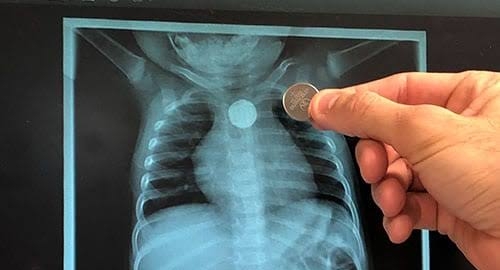

বোতাম ব্যাটারি গিলে বিপন্ন শিশুদের জীবন — সতর্ক থাকার আহ্বান চিকিৎসকদেরদেখতে ছোট্ট, ওজনেও হালকা। কিন্তু একটি বোতাম ব্যাটারি শিশুদের জন্য হয়ে উঠছে প্রাণঘাতী বিপদের কারণ। খেলনা গাড়ি, রিমোট, দেয়াল ঘড়ি, টর্চ কিংবা বিভিন্ন ইলেকট্রনিক ডিভাইসে ব্যবহৃত এই ব্যাটারি শিশুদের হাতে প্রায়শই চলে আসে। কৌতূহলবশত খেলতে খেলতেই অনেক ছোট শিশু এগুলো মুখে দিয়ে ফেলে—আর তখনই শুরু হয় ভয়াবহ বিপদের সম্ভাবনা।

চিকিৎসক বিশেষজ্ঞদের মতে, বোতাম ব্যাটারি যদি শ্বাসনালিতে আটকে যায়, শিশুর শ্বাস বন্ধ হয়ে মুহূর্তের মধ্যেই মৃত্যুও হতে পারে। আর যদি খাদ্যনালিতে ঢুকে যায়, ব্যাটারির ভেতরের রাসায়নিক পদার্থ খাদ্যনালির আস্তরণ পুড়িয়ে দেয়, রক্তক্ষরণ এমনকি ছিদ্রও করতে পারে। শরীরের ভেতরে ব্যাটারি যত বেশি সময় থাকে, ক্ষতি তত মারাত্মক হয়ে ওঠে।